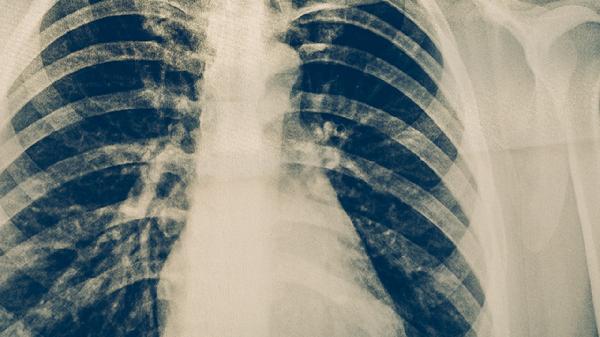

肺结核治愈一年通常可以跑步,但需根据个体恢复情况逐步增加运动强度。肺结核是由结核分枝杆菌感染引起的慢性传染病,经过规范抗结核治疗后,多数患者肺功能可逐渐恢复。

治愈一年后若复查显示肺部病灶完全吸收、无活动性病变且肺功能正常,可尝试低强度有氧运动如慢跑。初期建议选择平坦场地,控制心率在每分钟100-120次,单次持续时间不超过30分钟,每周3-4次为宜。运动时注意监测呼吸状态,出现胸闷气促应立即停止。恢复期跑步有助于改善心肺功能,但需避免剧烈运动导致过度换气。

若存在肺纤维化等后遗症或合并其他基础疾病,需经呼吸科医生评估后制定运动方案。部分患者可能因胸膜粘连出现运动后胸痛,或因残留病灶影响气体交换效率。这类情况建议优先选择游泳、太极拳等低冲击运动,跑步时应配备血氧监测设备,避免在高污染环境或寒冷天气户外运动。